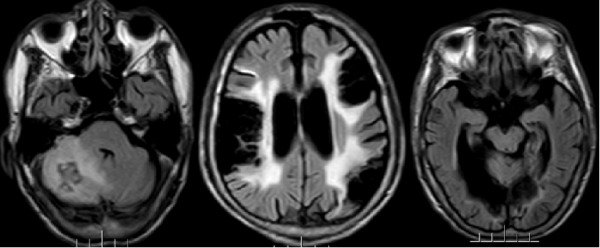

據林先生介紹,林大爺既往有高血壓、房顫病史。自2011年以來,曾三次因腦梗住院,並遺留了飲水嗆咳、肢體抖動等症狀。入院後,我院副院長、神經內科專家王展航為患者完善了相關檢查,發現他顱內有新的腦梗部位。為進一步明確病因,王展航又邀請了心理行為醫學科專家及康復醫學科專家進行會診。經討論分析,最終診斷患者為器質性精神障礙、右側小腦出血性腦梗死(亞急性)及腦梗死後遺症。

“腦梗死的發生影響到與情緒相關的部位。相關腦組織受到損害,引起器質性病變,從而導致患者出現精神障礙。”對於患者的“精神異常行為”,王展航也做了詳細解釋。